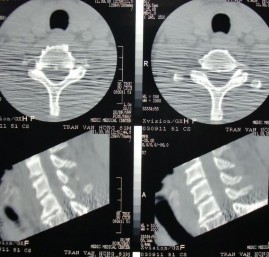

Họ tên: Tr.V. H, Tuổi: 63, Phái: Nam.

Địa chỉ: 639D Nguyễn trãi, P11, Q5, TP. HCM. Số hồ sơ: 459/2003. (Bệnh án số: 26).

Thời gian vào viện: 15 ngày. Thời gian đến lúc mổ: 25 ngày. Thời gian nằm viện: 12 ngày. Thời gian theo dõi: 102 tháng.

Nguyên nhân tai nạn: Tai nạn sinh hoạt. Cơ chế chấn thương: Cơ chế cúi.

Bệnh sử: Ngày 11-9-2003 té cao 1,5mm, va chẩm vào tường. Đau đơ cổ, không tổn thương thần kinh. X quang không thấy tổn thương. X quang cắt lớp điện toán cũng không phát hiện tổn thương. Được chẩn đoán là chấn thương phần mềm CSC. Điều trị thuốc giảm đau và đeo nẹp cổ. 2 tuần sau đau cổ nhiều hơn. Không

tổn thương thần kinh và X quang kiểm tra thấy di lệch C5 – C6 ra trước 4mm, gập góc + 220.

Chẩn đoán lâm sàng: Bong gân nặng C5 – C6. Frankel E.

Phương pháp phẫu thuật: Bohlman cải tiến (Chỉ 0,6mm dùng néo ép 2 mỏm gai và cố định mảnh xương ghép).

Kết quả điều trị: Nắn xương hoàn hảo, hết di lệch hoàn toàn. Góc gù - 20. Phục

hồi đường cong sinh lý CSC. Frankel E.

Liền xương độ I.

Độ đau VAS = từ 5 0 điểm.

Bệnh án này nhằm minh họa cho sự mất vững của tổn thương do bong gân nặng CSC thấp.

CT-SCAN SAU CHẤN THƯƠNG:

Không thấy tổn thương, ngang tầng C5-C6 bình thường

2 TUẦN SAU ĐIỀU TRỊ BẢO TỒN

Di lệch thứ phát ngang tầng C5-C6